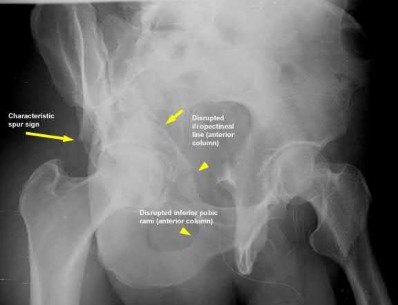

A 35-year-old patient is involved in a motor vehicle collision and sustains multiple injuries, including an APC pelvis fracture. He is stabilized following placement of a pelvic binder and receiving blood products as part of a massive transfusion protocol. He is subsequently taken to radiology for radiographs and a chest, abdomen, and pelvis CT with 4mm cuts. What effect will these modalities have on the radiographic appearance of his pelvis fracture and what further intervention should be performed?

1) Make the injury look more severe; obtained radiographs with the binder removed

2) Make the injury look less severe; perform fluoroscopic examination under anesthesia

3) Accurate representation of injury severity; no further studies needed

4) Make the injury look less severe; repeat CT with 0.625 mm cuts

5) Make the injury look more severe; obtain Judet views of the pelvis

Application of a pelvic binder and CT scans prior to standard AP pelvis radiographs results in an underestimation of pelvic ring injury severity. Since this patient was hemodynamically unstable and required a massive transfusion,

removal of the pelvic binder is not recommended and further injury stability should be evaluated by fluoroscopic examination under anesthesia.

Pelvic ring fractures are high energy injuries that usually follow motor vehicle collisions. There is a high rate of hemodynamic instability with these injuries due to the increase in pelvic volume and abundant venous bleeding. Proper identification of injury severity in the initial evaluation is crucial to ensure appropriate definitive treatment. Ideally, if the patient is hemodynamically stable, AP pelvis radiographs without a pelvic binder have been found to be effective at identifying unstable pelvic injuries.

Fagg et al. performed a retrospective study of 97 patients presenting with pelvic ring fractures requiring operative stabilization. The authors found that 7% of patients that initially had binder-on imaging were found to have unstable fractures that were not identified on the original images. The authors suggested that pelvic CT scans with the binder on are insufficient in determining the severity of pelvic fractures.

Swartz et al. performed a retrospective study of 43 patients presenting with pelvic ring fractures that received AP pelvic radiographs, pelvic binder, pelvic CT, and fluoroscopic stress examination in sequential order. They found that pre-binder radiographs had a greater sensitivity at detecting unstable fractures than pelvic CT with a binder. The authors concluded that placement of a binder prior to imaging can underestimate the severity of the pelvic injury and in cases where a binder is placed prior to imaging a fluoroscopic examination under anesthesia can be useful in detection.

Gibson et al. performed a retrospective review of 72 patients that presented with pubic diastasis requiring internal fixation. The authors found that pelvic CT scans without a pelvic binder underestimated the diastasis by 6.6mm compared to AP pelvic radiographs. The authors recommend obtaining radiographs prior to performing a CT, as underestimation of pubic diastasis can alter definitive management decisions.

Incorrect Answers:

Answer 1: Placement of a pelvic binder prior to radiographs and early CT scans underestimate the severity of pelvic ring injuries. In this case, the patient is hemodynamically unstable and removing the binder would likely result in increased pelvic bleeding by destabilizing clots.

Answer 3: The CT scan with the binder in place will underestimate the injury severity in this patient. In order to provide proper definitive care, the severity of the injury must be determined.

Answer 4: The current study has underestimated the degree of pelvic

instability. However, decreasing the cut thickness on CT will be unlikely to better determine the degree of pelvic ring instability.

Answer 5: The current injuries are underestimated by the current image study regimen with binder placement. Judet views, especially with the binder in place, will not enhance the detectability of pelvic ring instability.